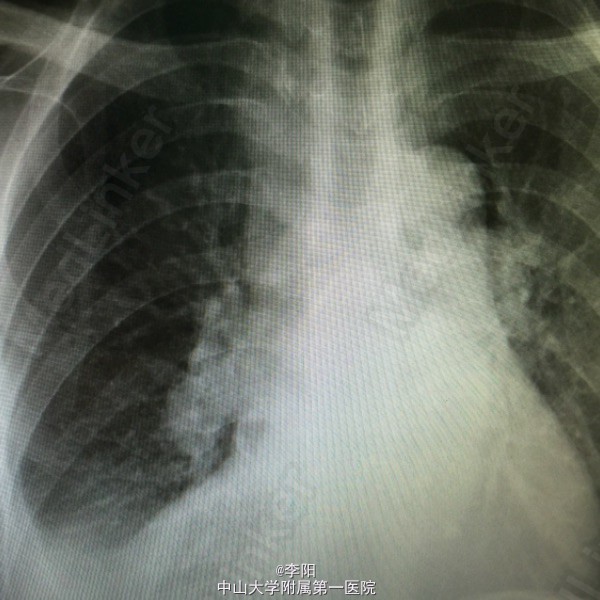

风湿性心脏病一例

风湿性心脏病

患者3月前无明显诱因出现活动后气促,气喘,伴活动耐量下降,伴双下肢凹陷性水肿,无咳嗽,咳痰,呼吸困难,,b超提示:风湿性心脏病,二尖瓣中度狭窄,左房增大,左心功能减低。